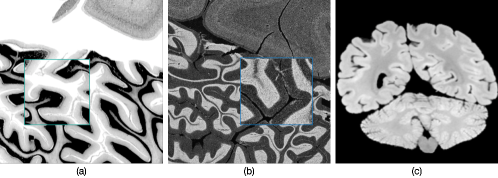

Recent advancements in convolutional neural networks (CNNs) have shown significant progress in computer-aided medical imaging analysis [1, 2, 3]. However, obtaining expert-level annotations for medical datasets is expensive and time-consuming, particularly for high-resolution histology data [4, 5], such as the BigBrain atlas [6], an open-source 3D human brain model for which a comprehensive cerebellum segmentation is lacking. Unlike the common 1mm MRI, BigBrain atlas is scanned at 20µm to visualize the highly compact and convoluted cerebellar foliations (as shown in Figure 1 (a) and (c)). Expert manual annotation of the cortical structures is time-consuming [7].

To address this limitation, unsupervised domain adaptation (UDA) is a popular approach that transfers annotation knowledge from an existing labelled dataset (the source domain) to an unlabelled target domain [8, 9, 10, 11]. In this work, we explore unsupervised semantic segmentation for the BigBrain (BB) cerebellum, using the Allen Brain atlas [12] (AB) as the source domain. However, this task presents additional challenges. First, each domain only contains cerebellum sections from a single subject, and these two subjects are demographically distinct. This heterogeneous nature results in large domain variance. Second, images in the two domains use different staining methods to visualize neurons, resulting in visual discrepancies. as indicated in Figure 1: different color intensity distribution, the presence of noise in AB, and damage in BB. Semantic segmentation in medical imaging primarily relies on low-level features (texture, intensity, etc.) [8]. Discrepancies in these low-level features bring extra challenges. Lastly, there are only 24 annotated cerebellum sections in AB. Without abundant data, it is hard for the model to generalize well on the target dataset.